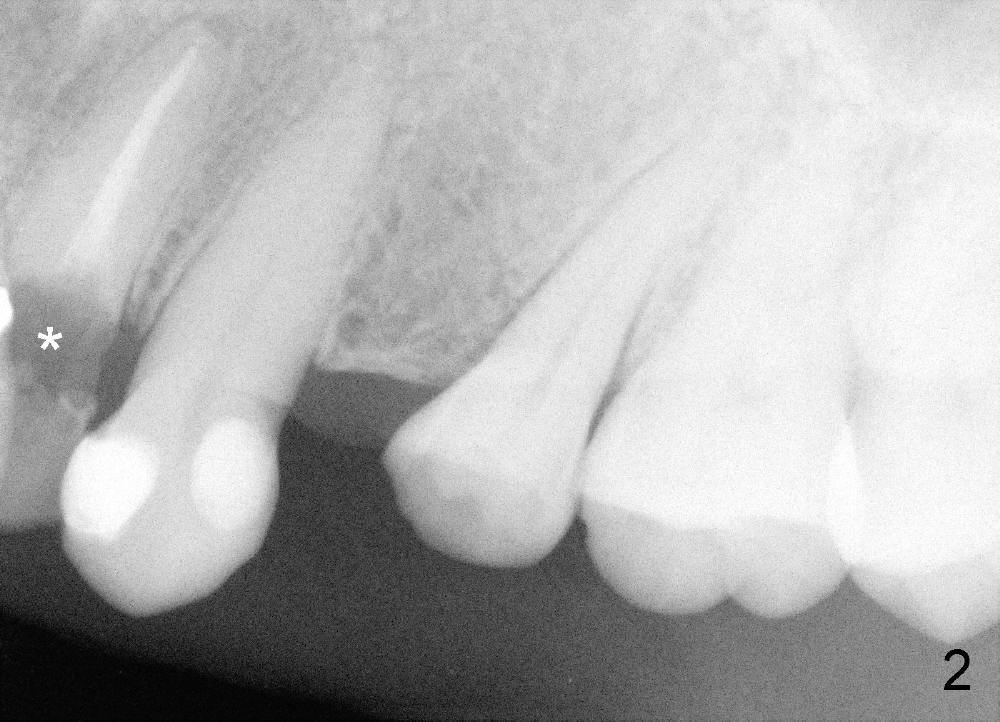

A fifty five year old lady requests implant restoration for the upper left lateral incisor after the crown fractures (Fig.3*). X-ray in Fig.1,2,4 were taken before loss of the crown. The biggest issue is the narrow space of this lateral mesiodistally (Fig.3).